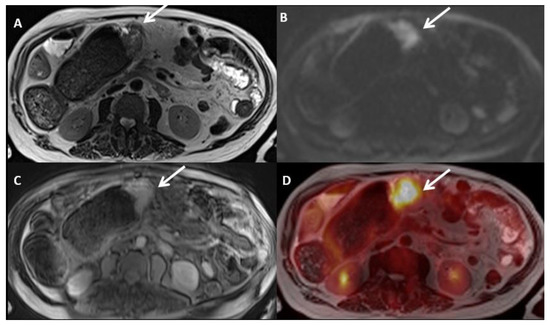

2.2. Magnetic Resonance Imaging (MRI)

2.3. Positron Emission Tomography (PET)-CT

2.4. Imaging Combination